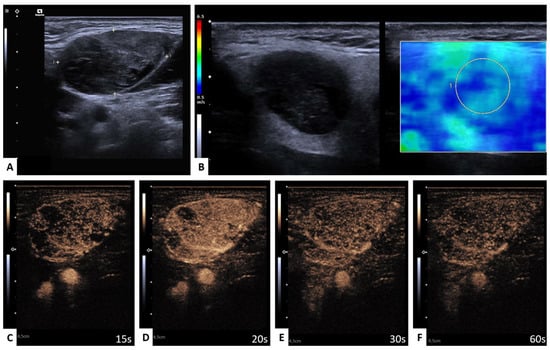

2.4. Perfusion Analysis

3.4.1. WT versus PA